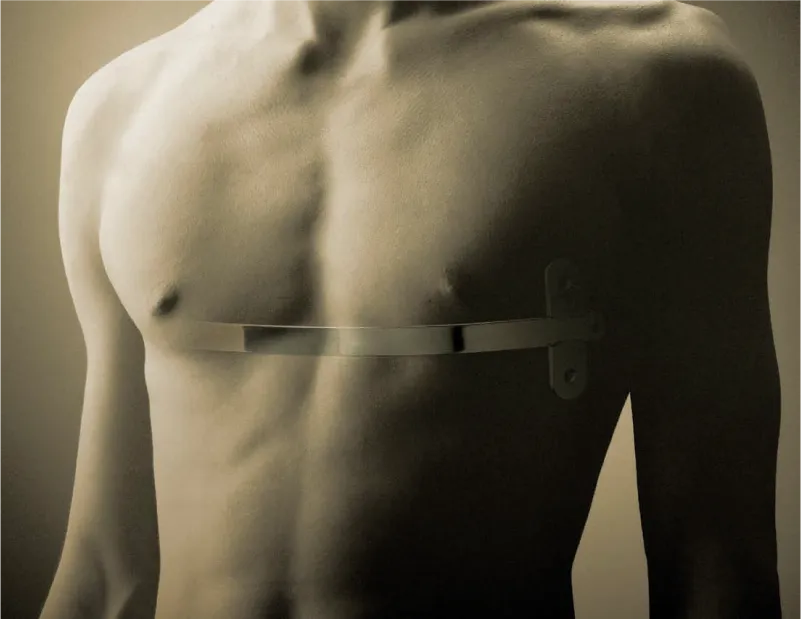

Barras Pectus

El pectus excavatum (también conocido como síndrome del pecho hundido) no se puede prevenir, pero es tratable.